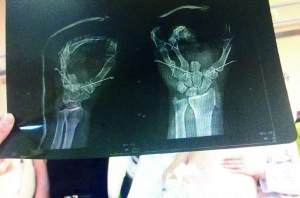

昨天下午,记者来到了朝阳急诊抢救中心的住院部,在外伤病房内,记者看到了病床上的刘成超。他的右手完全包裹着白色的纱布,完全无法使用。他告诉记者,目前他只能用左手做事情,现在手中已经打进了三个钢钉(见图),至于以后自己的手掌是什么样的结果,他也不知道。